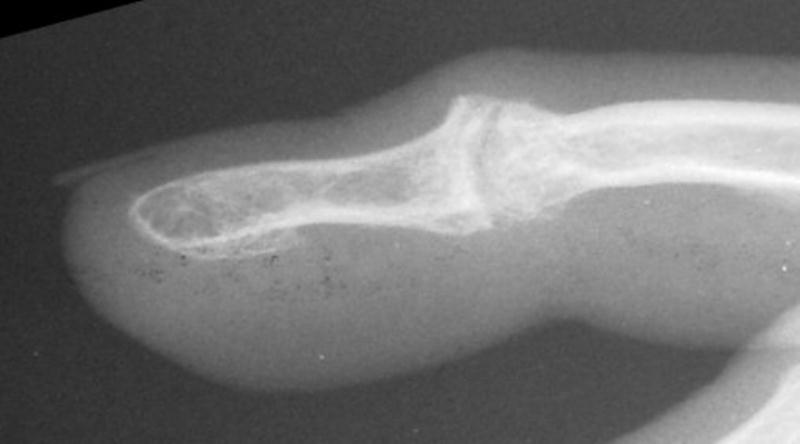

The trial implant sizer shows the true size of the implant. The final implant has a radiolucent coating  which makes it appear smaller than it is on Xray.

Final implant radiographs.

Xrays one year out.